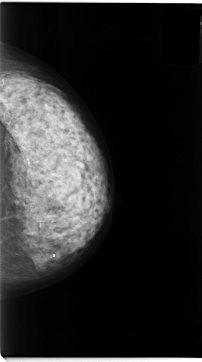

C_0052_1.LEFT_MLO

C_0052_1.LEFT_CC

LEFT_CC LINES 4704 PIXELS_PER_LINE 2616 BITS_PER_PIXEL 12 RESOLUTION 50 NON_OVERLAY

LEFT_MLO LINES 4672 PIXELS_PER_LINE 2832 BITS_PER_PIXEL 12 RESOLUTION 50 NON_OVERLAY